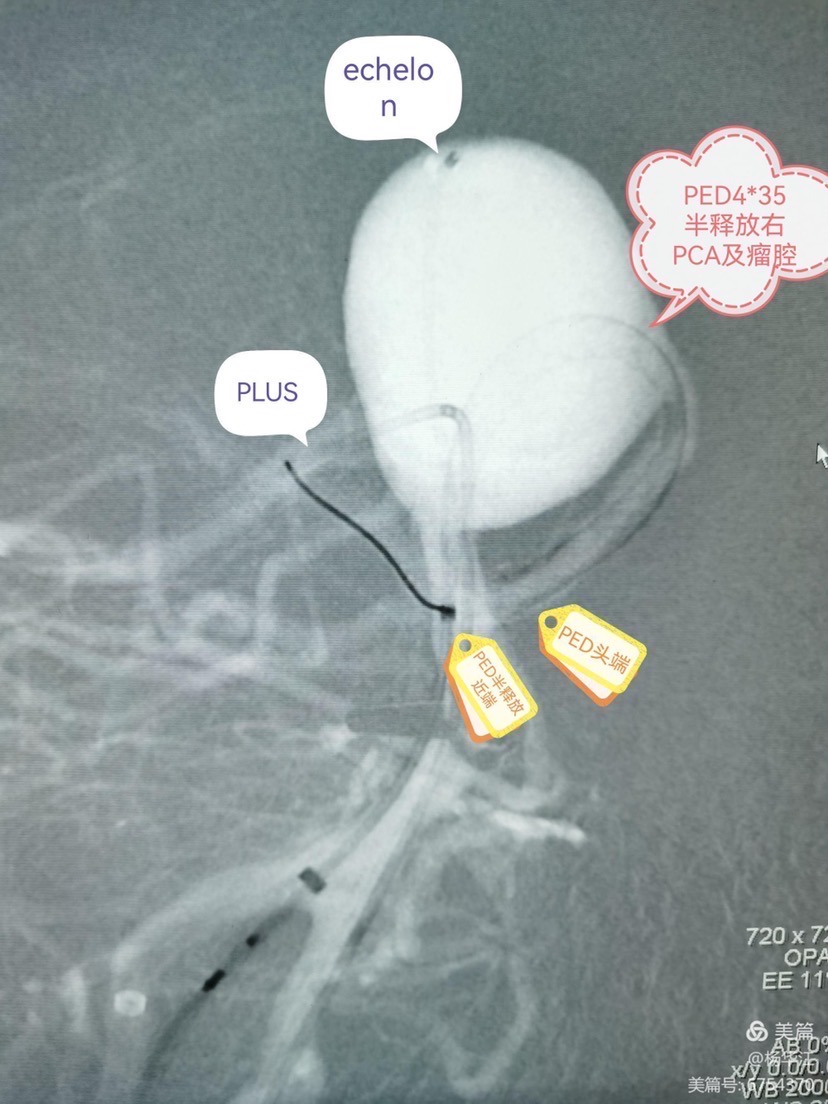

先echelon10微导管瘤内成襻技术超选入右侧大脑后动脉远端,拉直解襻微导管,交换phenom导管到右侧大脑后动脉远端,由于瘤颈超宽,导管再次疝入成襻才能超选至右侧大脑后动脉远端。

4.0x35pipeline经成襻的phenom导管缓慢送人右侧大脑后动脉远端,锚定,缓慢半释放至基底动脉中上段。

然后填圈至动脉瘤中、上部致密填塞,下部近分支处疏松填塞,同时释放左侧EP2支架,尾端紧贴pipeline侧方呈T形放置。最后稍推拉完全pipeline至基底动脉中下段。(这是本次手术有瑕疵的地方,尾端覆盖基底动脉稍长了一些,与我们测量计算误差有关)